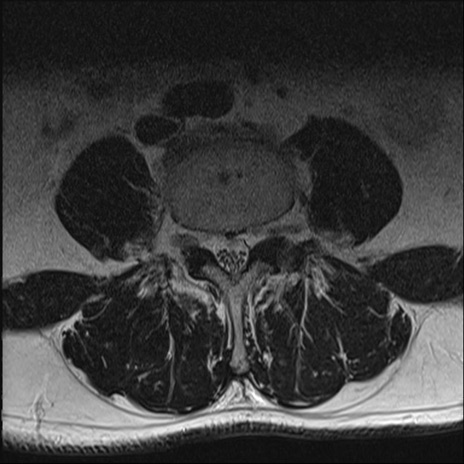

【整形】TIPS症例2 腰椎MRI T2WI(横断像)

【症例】70歳代男性

【主訴】左下肢痛

【現病歴】2週間前くらいから腰痛、左下肢痛あり。左臀部から大腿、下腿外側のしびれが常時ある。歩行とともに同部位の痛みあり。

【身体所見】Lasegue70-/60+、Bragard-/±、PTR ±/±、ATR -/-、IP 5/5、TA 5/4、TS 5/5、EHL 右第1足趾なし/3、FHL 5/5、hypersthesia(-)、足背動脈触知良好

異常所見と診断は?